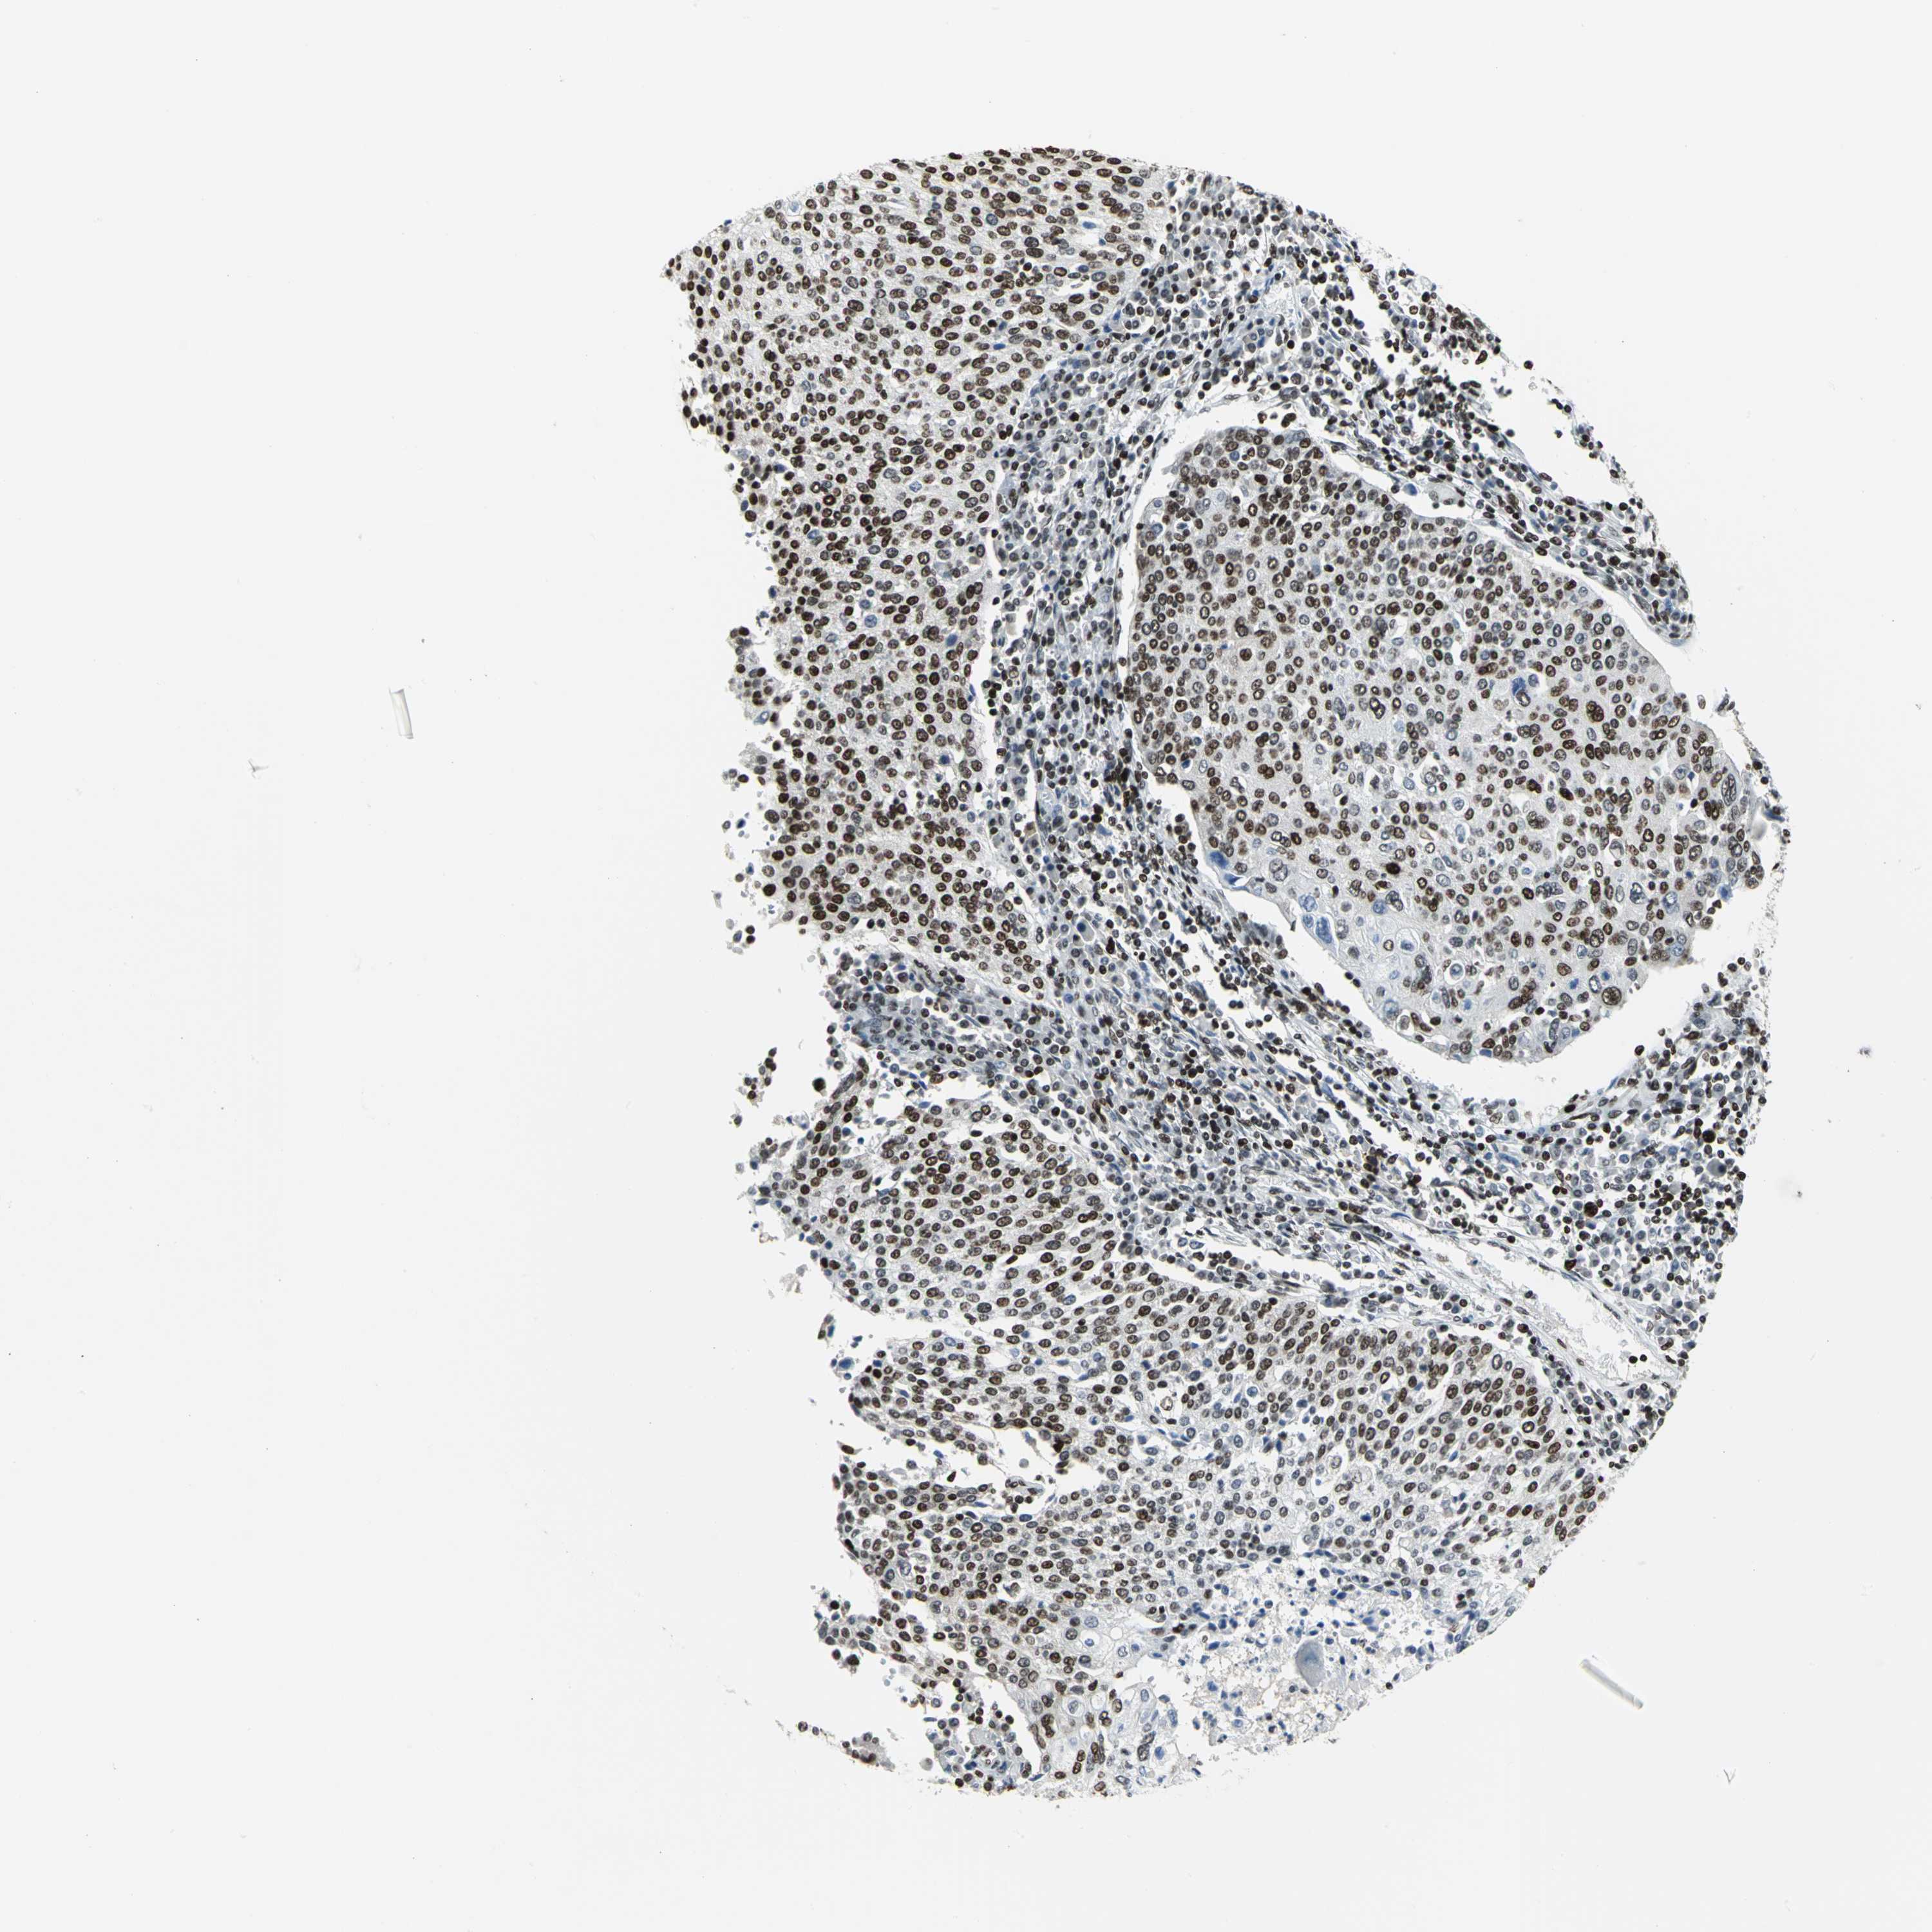

CERVICAL CANCER - Protein expressioni

A mouse-over function shows sample information and annotation data. Click on an image to view it in a full screen mode. Samples can be filtered based on level of antibody staining by selecting one or several of the following categories: high, medium, low and not detected. The assay and annotation is described here.

Note that samples used for immunohistochemistry by the Human Protein Atlas do not correspond to samples in the TCGA dataset.

Antibody stainingi

Antibody staining in the annotated cell types in the current human tissue is reported as not detected, low, medium, or high, based on conventional immunohistochemistry profiling in selected tissues. This score is based on the combination of the staining intensity and fraction of stained cells.

Each image is clickable and will lead to virtual microscopy that enables deeper exploration of all samples and also displays staining intensity scores, fraction scores and subcellular localization as well as patient and tissue information for each sample.

Antibody HPA004911

Staining

High

Medium

Low

Not detected

Intensity

Strong

Moderate

Weak

Negative

Quantity

>75%

75%-25%

<25%

None

Location

Nuclear

Cytoplasmic/membranous

Cytoplasmic/membranous,nuclear

Squamous cell carcinoma, NOS

Adenocarcinoma, NOS